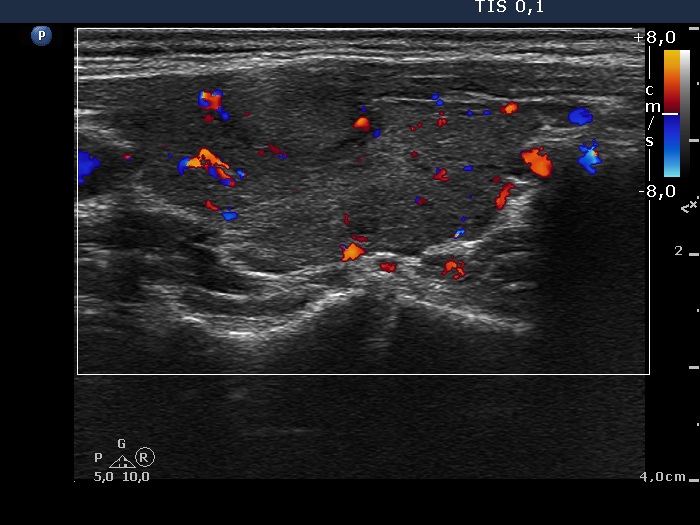

Discrete lesion or nodule in Hashimoto's thyroiditis - case 9 (644) (ultrasonographic picture 8)

Left lobe, longitudinal scan, color Doppler mode.